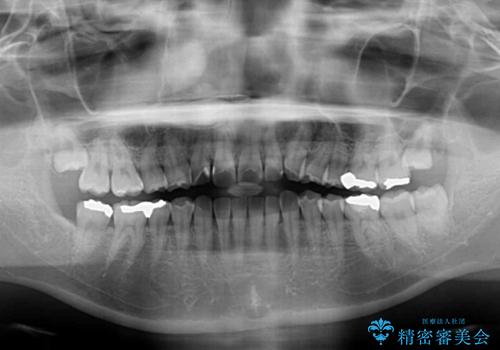

上下前歯のデコボコを気にして来院された患者様です。

舌の突出癖により、治療過程でスペースが多くできましたが、舌のトレーニングを頑張っていただき、1年強で終えることができました。

- 症状により、抜歯が必要な場合があります